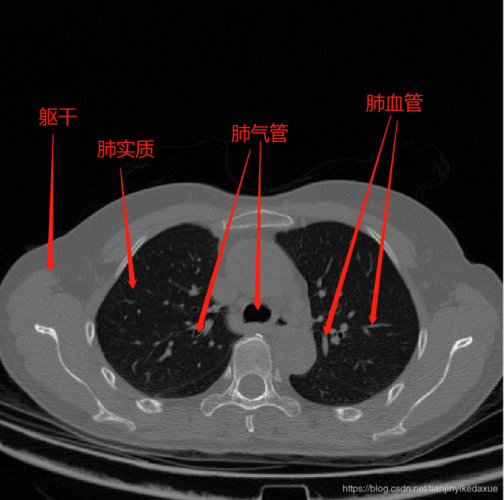

首先,展示一张肺部ct图像,从直观上介绍一下